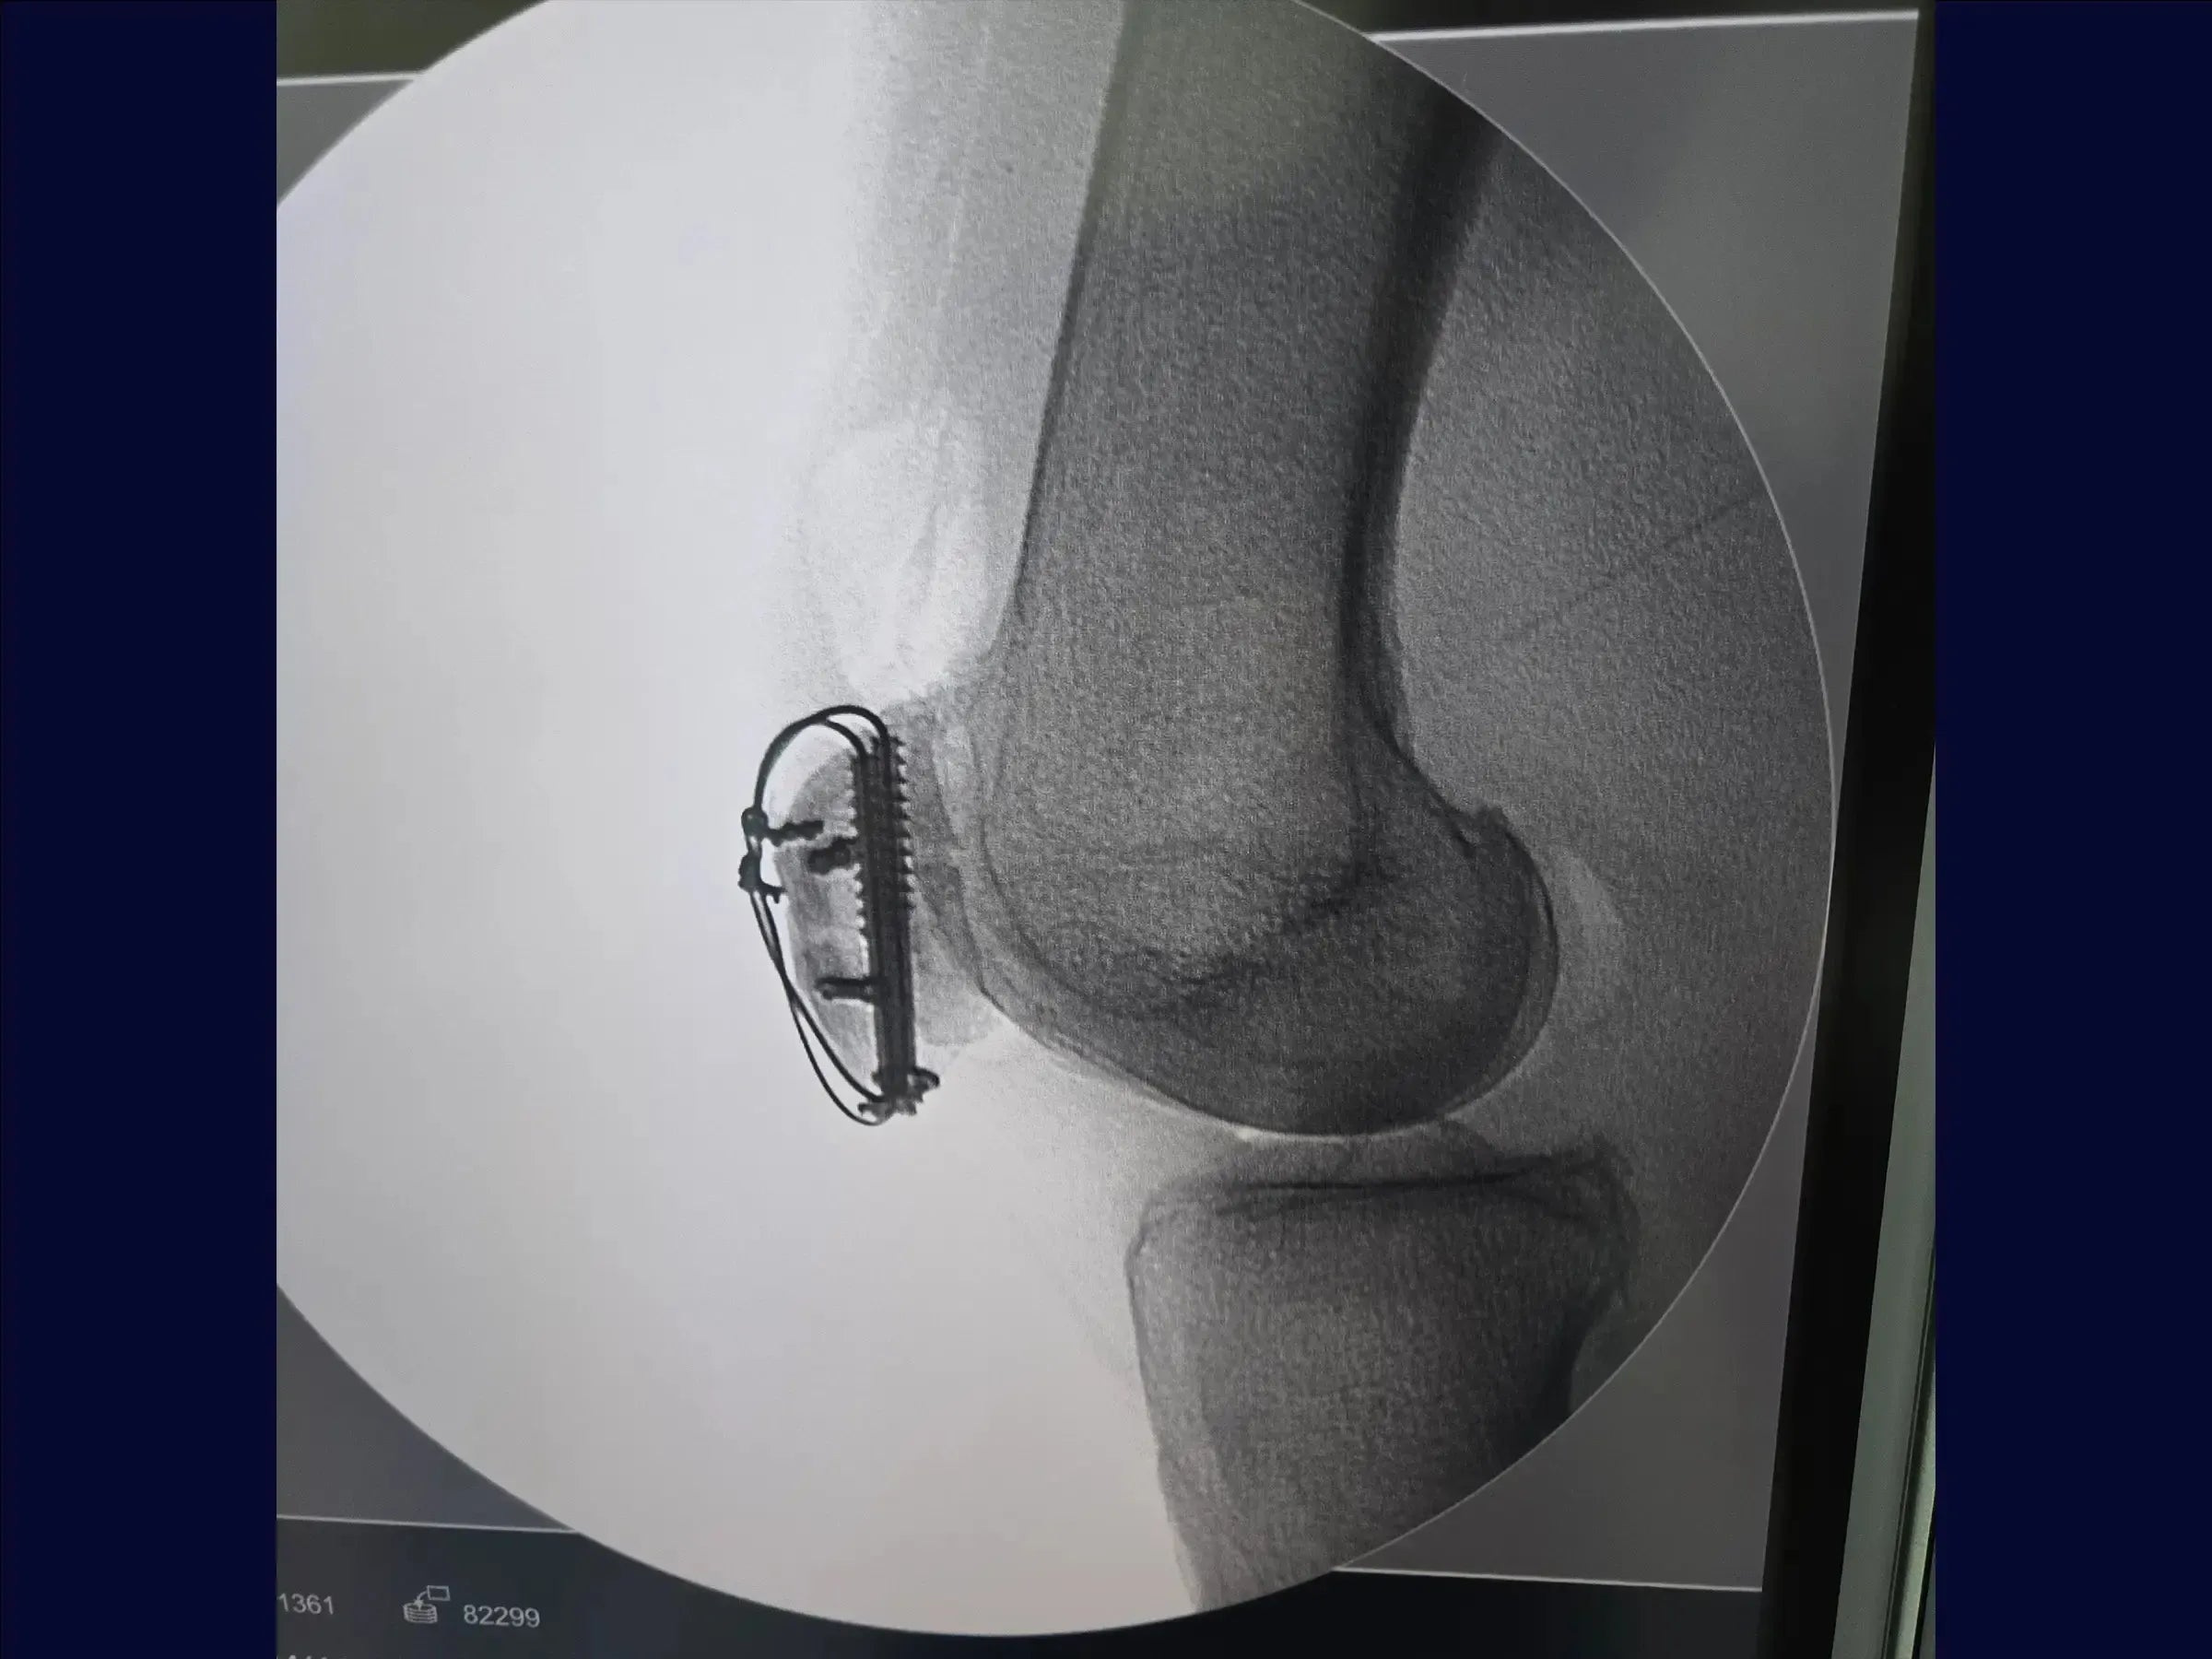

- Uso de parafusos canulados e cerclagem.

- Fixação de Fragmentos Laterais: Utilização de parafusos de dupla compressão para fixação de fragmentos na aleta lateral, com sepultamento completo da cabeça para prevenir proeminência do implante.

- Identificação do Fragmento Chave: Foco na importância do polo inferior inserido ao tendão patelar como ponto crucial para a redução e concentração de parafusos com arruela para estabilização.

- Prevenção de Complicações: Estratégias para evitar instabilidade pós-fixação e considerações sobre a proeminência de implantes, especialmente placas em patela, que frequentemente necessitam de remoção.